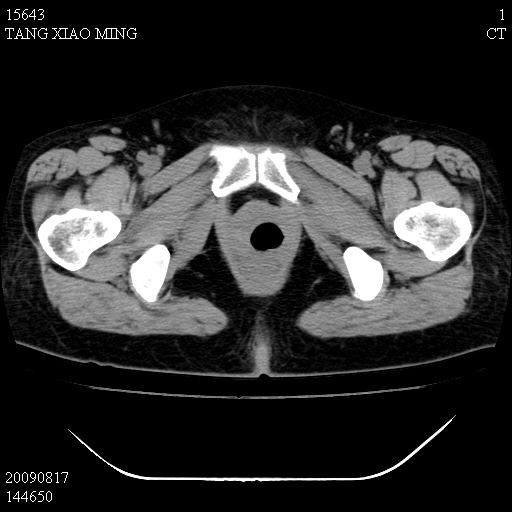

标题: CT21692:盆腔病变

女,33岁,右下腹痛2年余,既往宫外孕病史,如在我院手术,结果下周公布,

可能的诊断。1子宫内膜异位【子宫腺肌症并右卵巢巧克力囊肿】;2 右卵巢囊腺瘤。子宫肌瘤

1)考虑卵巢巧克力囊肿,不排除卵巢囊腺瘤。2)子宫肌瘤可能。

卵巢囊腺瘤,子宫肌瘤,直肠壁厚,不除外占位.